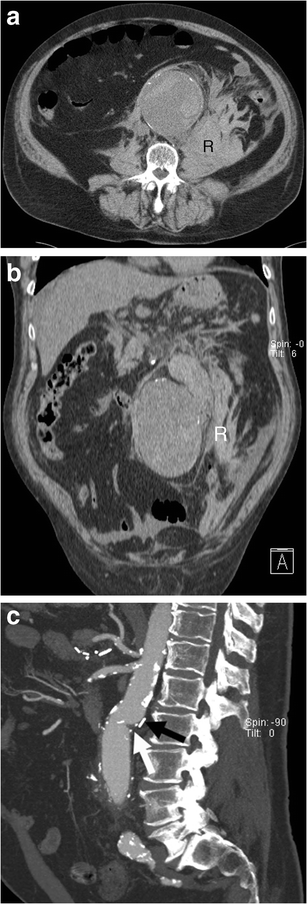

Aortocaval fistula. a Axial arterial phase enhanced CT shows simultaneous enhancement of the AAA and IVC in an 83-year-old man with AAA rupture and retroperitoneal haematoma (R). b Axial enhanced CT of the same patient at a lower level demonstrates active contrast extravasation (white arrows) from the aortic aneurysm to the IVC with loss of normal fat planes between the structures. Retroperitoneal haematoma (R) can also be seen

Open surgical repair. a Axial and b coronal unenhanced CT image of a 73-year-old man demonstrates ruptured AAA with a retroperitoneal haematoma (R). c Sagittal enhanced CT image of the same patient after successful open surgical repair shows the junction between the native aorta and aortic graft (white arrow) and a surgical clip (black arrow)